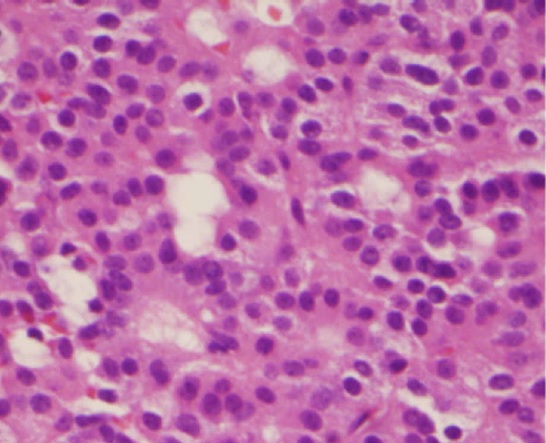

• Pituitary Adenoma

Pituitary Adenoma. True null cell adenomas are typically composed of uniform, mildly atypical cells with chromophobic cytoplasm. This case has papillary architecture similar to gonadotroph adenomas.[53] Juliana Drummond, Federico Roncaroli, Ashley B. Grossman, and Ma´ rta Korbonits. not altered. CC BY 4.0